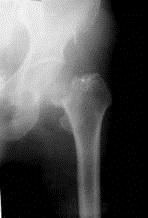

病历摘要: 患者××,女性,70岁,不慎跌倒致伤左髋部后疼痛、活动障碍2天。查体:左下肢呈屈髋屈膝及外旋畸形,右下肢活动时左髋部疼痛,左足跟和大粗隆有叩击...

问题 病历摘要: 患者××,女性,70岁,不慎跌倒致伤左髋部后疼痛、活动障碍2天。查体:左下肢呈屈髋屈膝及外旋畸形,右下肢活动时左髋部疼痛,左足跟和大粗隆有叩击痛。 人工全髋关节的适应症有哪些?

选项 A、关节成形术失败病例 B、骨肿瘤 C、65岁以上新鲜头下型股骨颈骨折 D、股骨头缺血性坏死 E、陈旧性股骨颈骨折 F、髋关节强直 G、慢性髋关节脱位 H、退行性骨关节炎 I、类风湿关节炎及强直性脊柱炎

答案 ABCDEFGHI